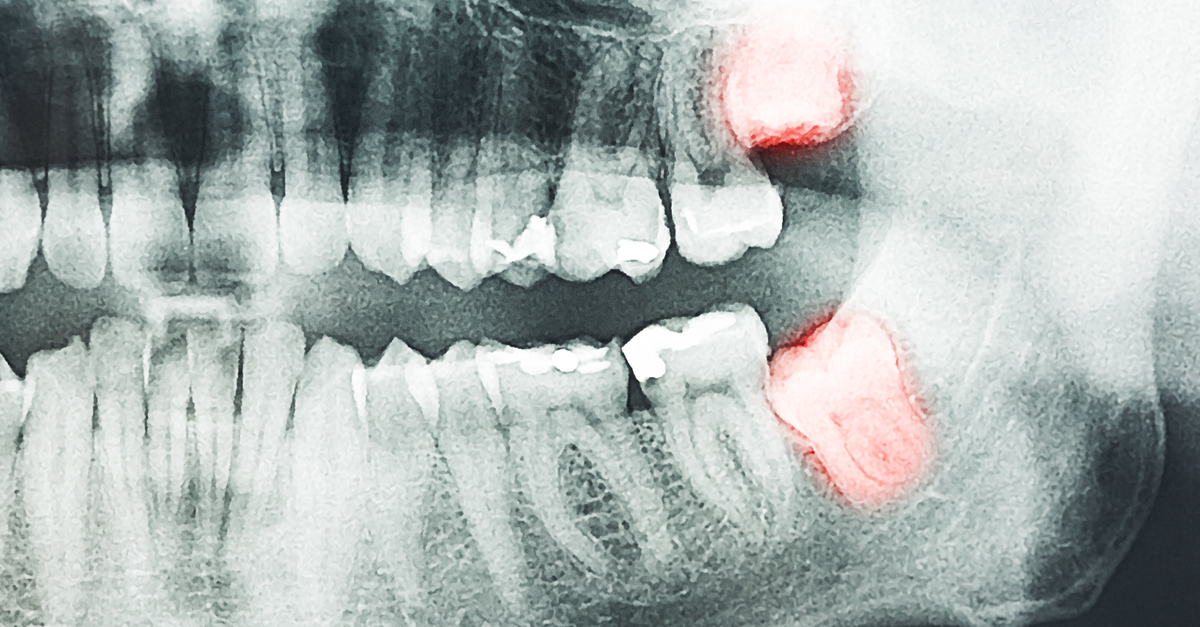

Diagnosing Incidental Thyroid Calcifications on Dental Images Dental X Rays Thyroid Cancer With the objective to inform clinical practice and guidelines, we synthesized the current epidemiological evidence on the association. Memon a, godward s, williams. Dental X Rays Thyroid Cancer.